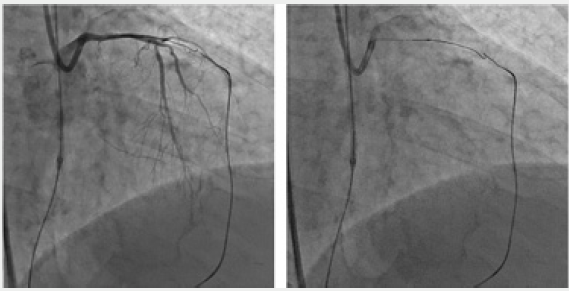

Figure 3: Retrograde recanalization of service stations. The technique of kissing wires (kissing wire crossing). Occlusion LIV. Bifemoral cannulation. From the PCA system, through the septal collaterals, a conductor “Sion” and a microcatheter “Corsair” were conducted. The microcatheter “Finecross” and the conductor “filder Fc” are antegradeally applied.